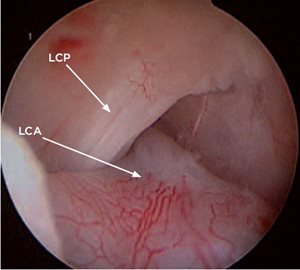

• elle montre si la rupture du ligament croisé est complète ou partielle (Photo 7) ;

Photo 7 : Rupture complète du ligament croisé antérieur.

LCP : ligament croisé postérieur

LCA : ligament croisé antérieur.